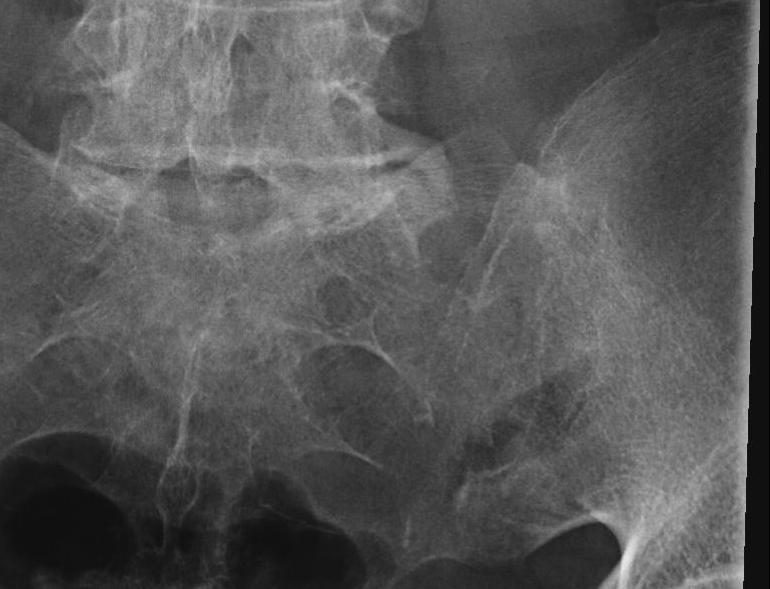

3. Xray changes